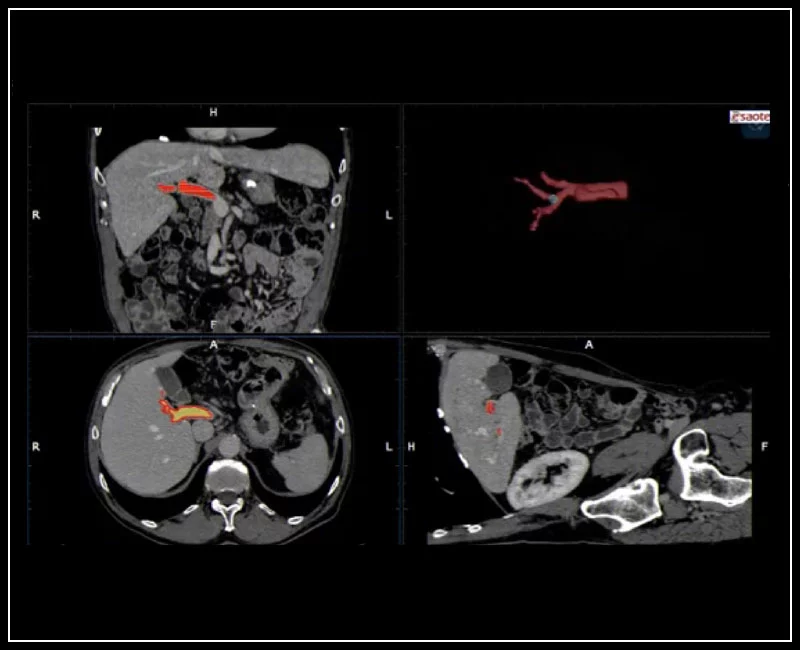

MyLab™9 Platform - Virtual Navigator automatic vascular detection and segmentation with Auto-Fusion

MyLab™9 Platform - Virtual Navigator automatic vascular detection and segmentation with Auto-Fusion